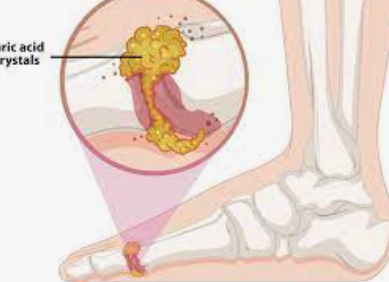

통풍은 혈중 요산 수치가 높은 사람들에게서 발생하는 일종의 염증성 관절염입니다. 산 (acid)은 관절에서 바늘 모양의 결정을 형성할 수 있으며 갑작스럽고 심각한 통증, 압통, 발적, 온감 및 부종을 유발할 수 있습니다. 통풍은 여성보다 남성에게 더 흔하며 종종 비만, 고 콜레스테롤, 고혈압 및 당뇨병과 같은 다른 질병 및 상태와 관련이 있습니다. 따라서 통풍 증상을 이해하고 있는 것은 중요하다고 할 수 있습니다.

1. 무증상 고요산혈증: 이 단계에서는 통풍 증상이 없지만 요산 수치가 높고 관절에 결정이 형성됩니다.

2. 급성 통풍 또는 통풍 발작: 이 단계는 무언가가 요산 수치를 급증시키거나 관절에 형성된 결정을 밀쳐 발작을 유발할 때 발생합니다. 급성 통풍 발작의 통풍 증상은 강렬하며 일반적으로 밤에 발생합니다.